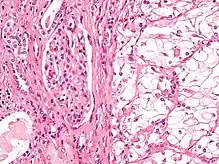

| Micrograph showing the most common type of kidney cancer (clear cell renal cell carcinoma). H&E stain. | |

The most common type of kidney malignancy is renal cell carcinoma,[34] which is thought to originate from cells in the proximal convoluted tubule of the nephron.[15][35] Another type of kidney cancer although less common, is transitional cell cancer (TCC) or urothelial carcinoma of the renal pelvis.[36] The renal pelvis is the part of the kidney that collects urine and drains it into a tube called the ureter.[36] The cells that line the renal pelvis are called transitional cells, and are also sometimes called urothelial cells. The transitional/urothelial cells in the renal pelvis are the same type of cells that line the ureter and bladder. For this reason TCC of the renal pelvis is distinct from RCC and is thought to behave more like bladder cancer.[36] Other rare types of kidney cancers that can arise from the urothelial cells of the renal pelvis are squamous cell carcinoma and adenocarcinoma.[15]

Renal cell carcinoma has been further divided into sub-types based on histological features and genetic abnormalities. The 2004 WHO Classification of the Renal Tumors of the Adults describes these categories:[40]

- Clear cell RCC